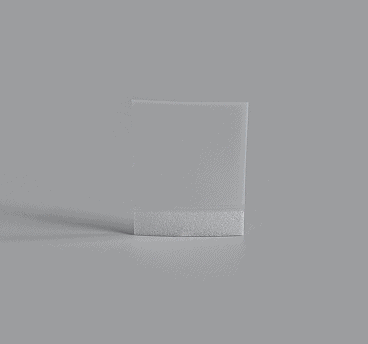

Sheet

Channel Sheet

Signle Channel Sheet